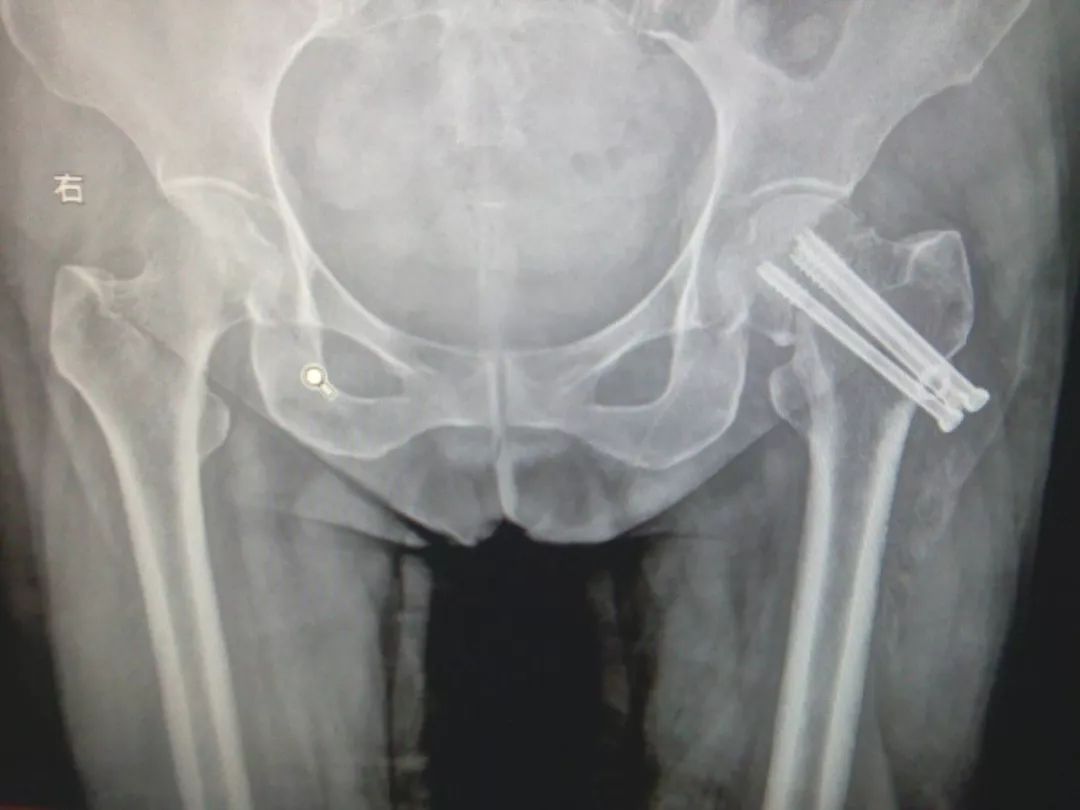

粗隆间骨折,骨质疏松,把持力不良,钉板固定,螺钉切割失败。